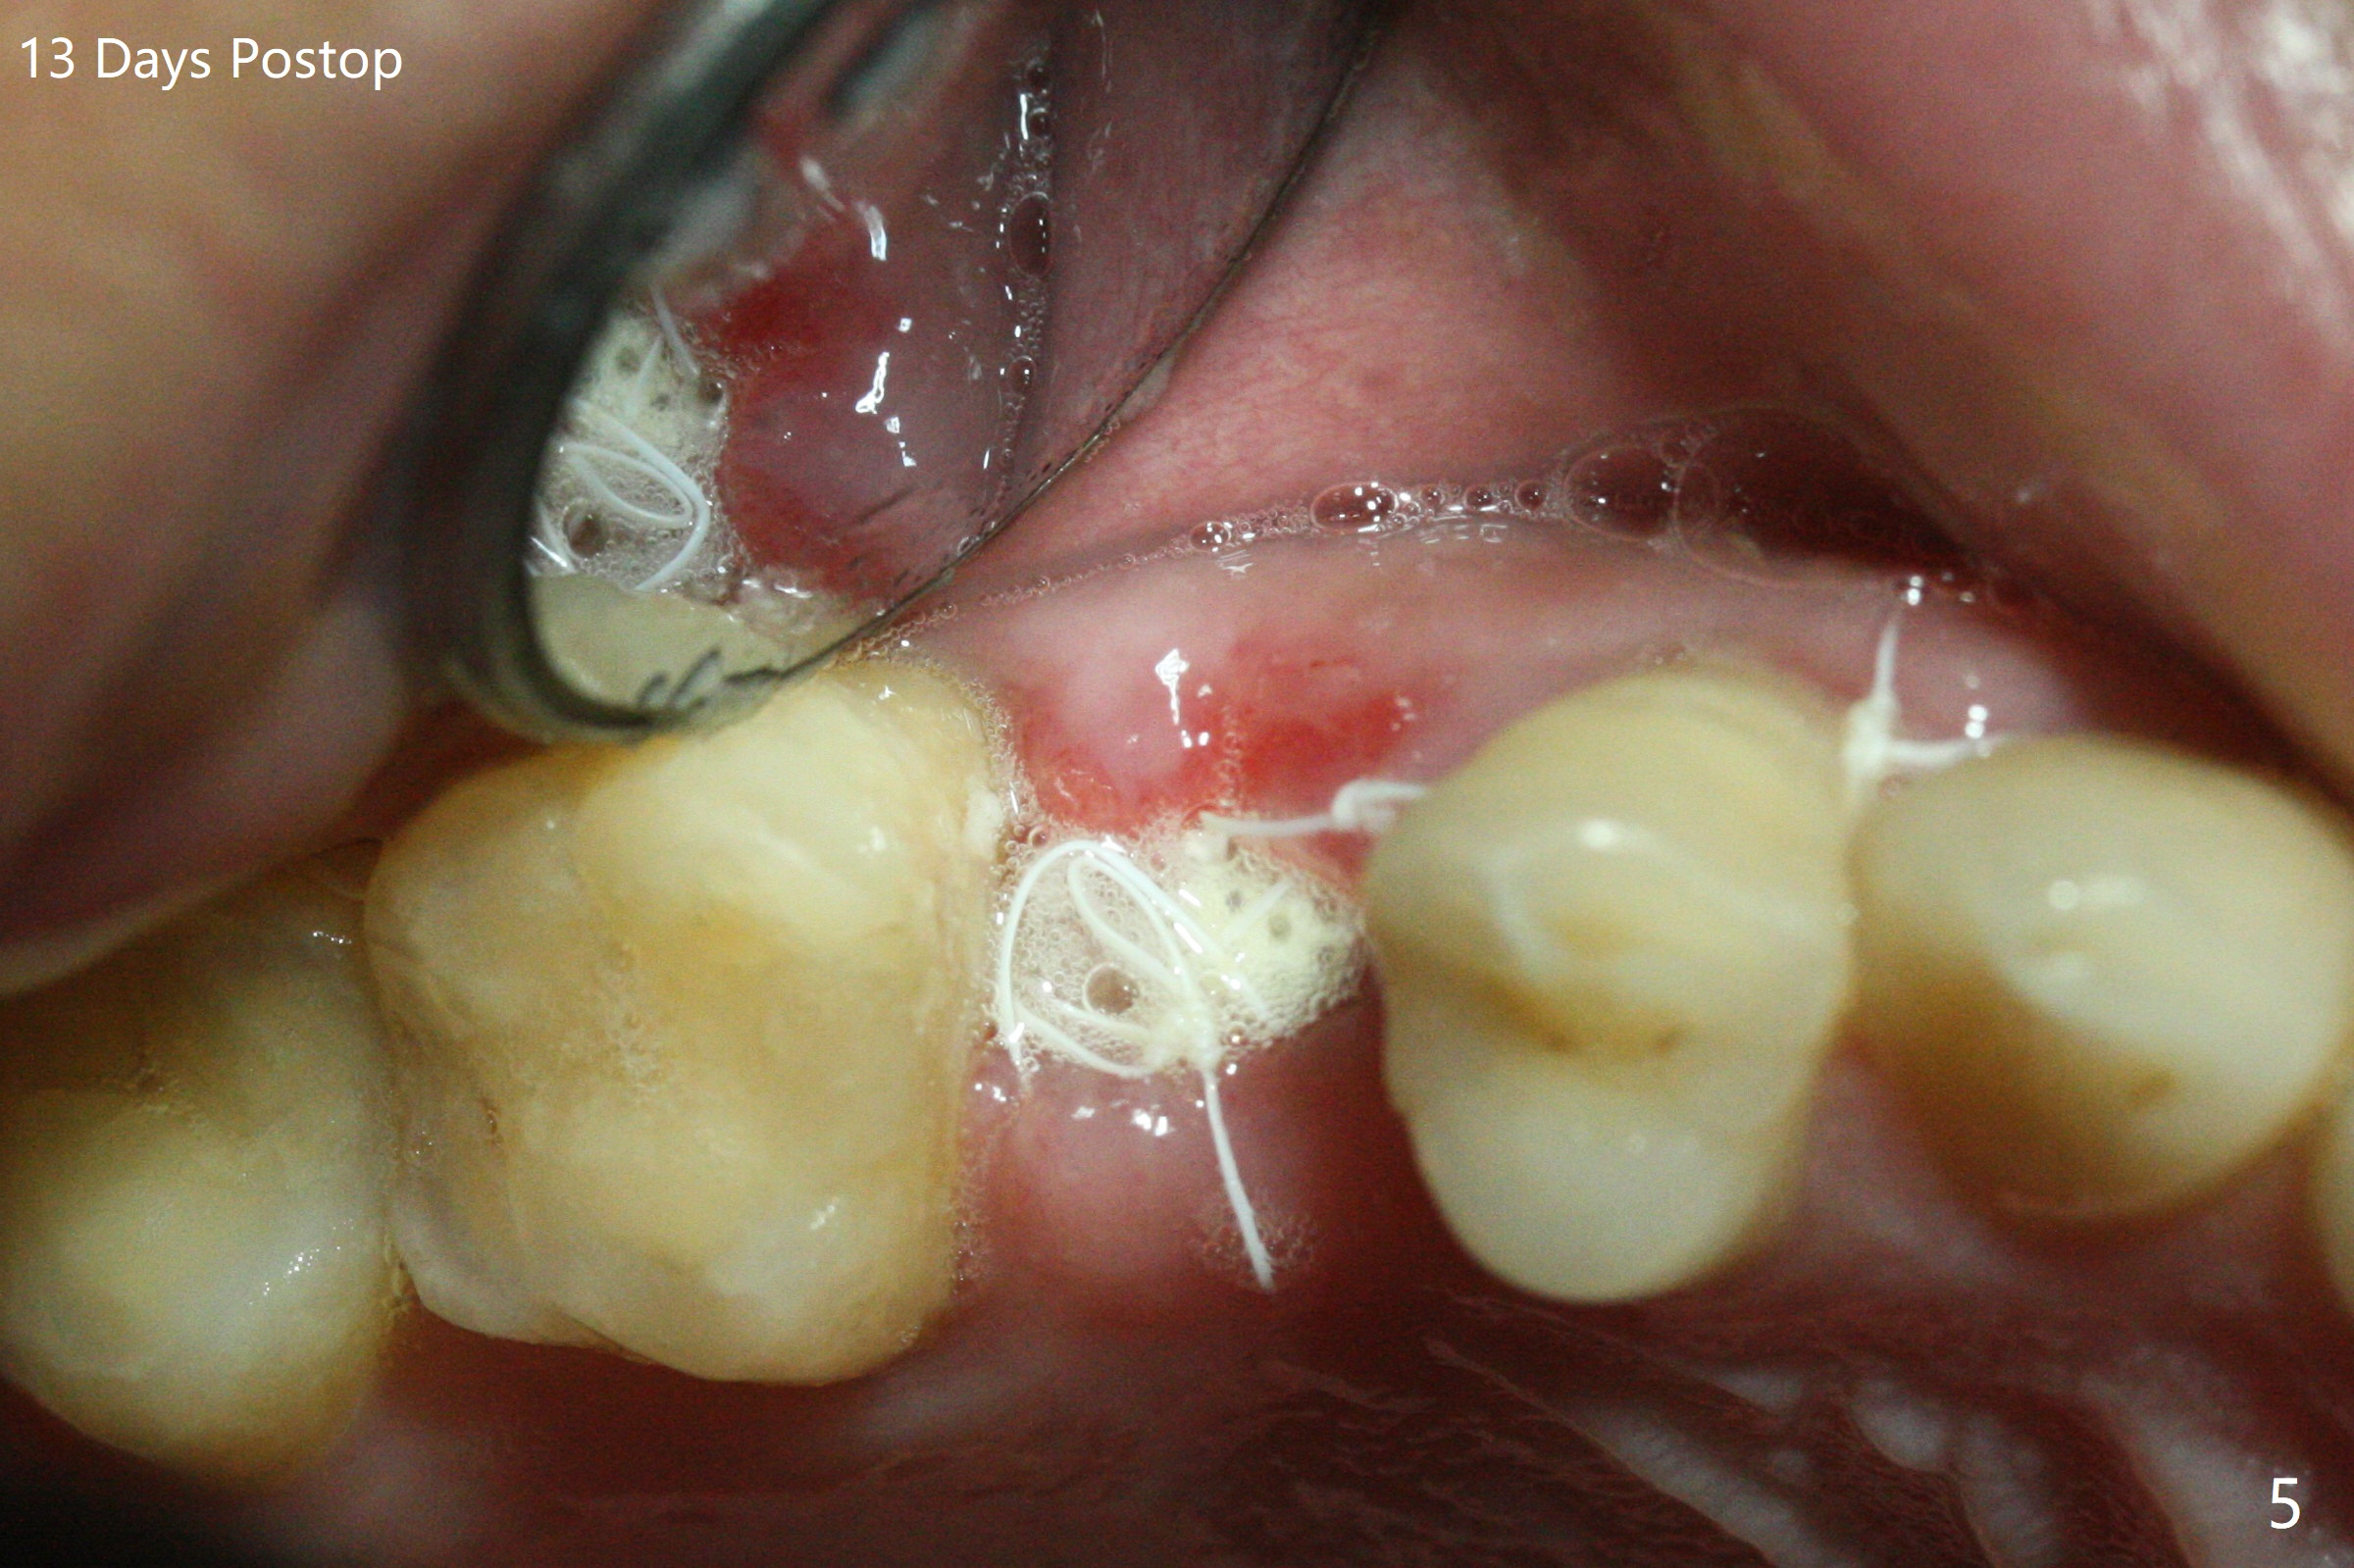

尽管没有任何症状,右上5牙冠粘固后2年5个月,牙冠与基台取出(没有使用扳手,说明基台未完全就位),切开,去除少量肉芽组织,仍然发现植体螺纹暴露(图一),使用一种叫I Brush 钛合金刷子清洁后,放置粘性骨块(图二: S),它坐在牙槽嵴上仿佛非常安稳,多么象马鞍(Saddle)。覆盖一张PRF膜和一小张Cytoplast(不可吸收膜,Osteogenics (company) 图三:箭头),使用PTFE缝线(与Cytoplast同样一种材料)缝合。术后即刻根尖片显示骨粉服服帖帖地坐落在植体和牙槽嵴上(图四:*)。最后覆盖牙周敷料。后者术后十天左右脱落,伤口愈合正常,颊侧瘘道仿佛消失,颊侧骨壁好像不再凹陷了(图五,六)。术后5周,膜已经脱落,缝线撤除后,伤口好像二期愈合,但愿肉芽组织下面骨粉尚未损失太多。术后三个月根尖片显示骨粉减少(图八)。不可吸收膜脱落可能造成骨粉流失。应该做减张缝合。术后4.5个月颊侧骨壁又凹陷(图九:箭头,需要decortication),但是uncover时植体周围都有骨质包绕,术后咬翼片也证明近中,远中骨质接触植体(图十:由于找不到合适愈合基台,直接放置基台和牙冠)。粘固后2.5个月虽然颊侧骨板凹陷,但是没有植体周围炎迹象(图十一)。